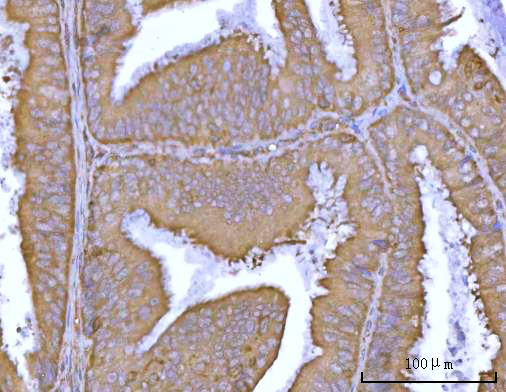

Widely expressed in adult and fetal tissues; very highly expressed in tumor cell lines such as HeLaS3, K-562, HL-60, SW480, A-549 and G-361; highly expressed in heart, peripheral blood lymphocytes, liver, pancreas, spleen, thymus, prostate, ovary, uterus, placenta, testis, esophagus, stomach and throughout the intestinal tract; not detectable in brain.